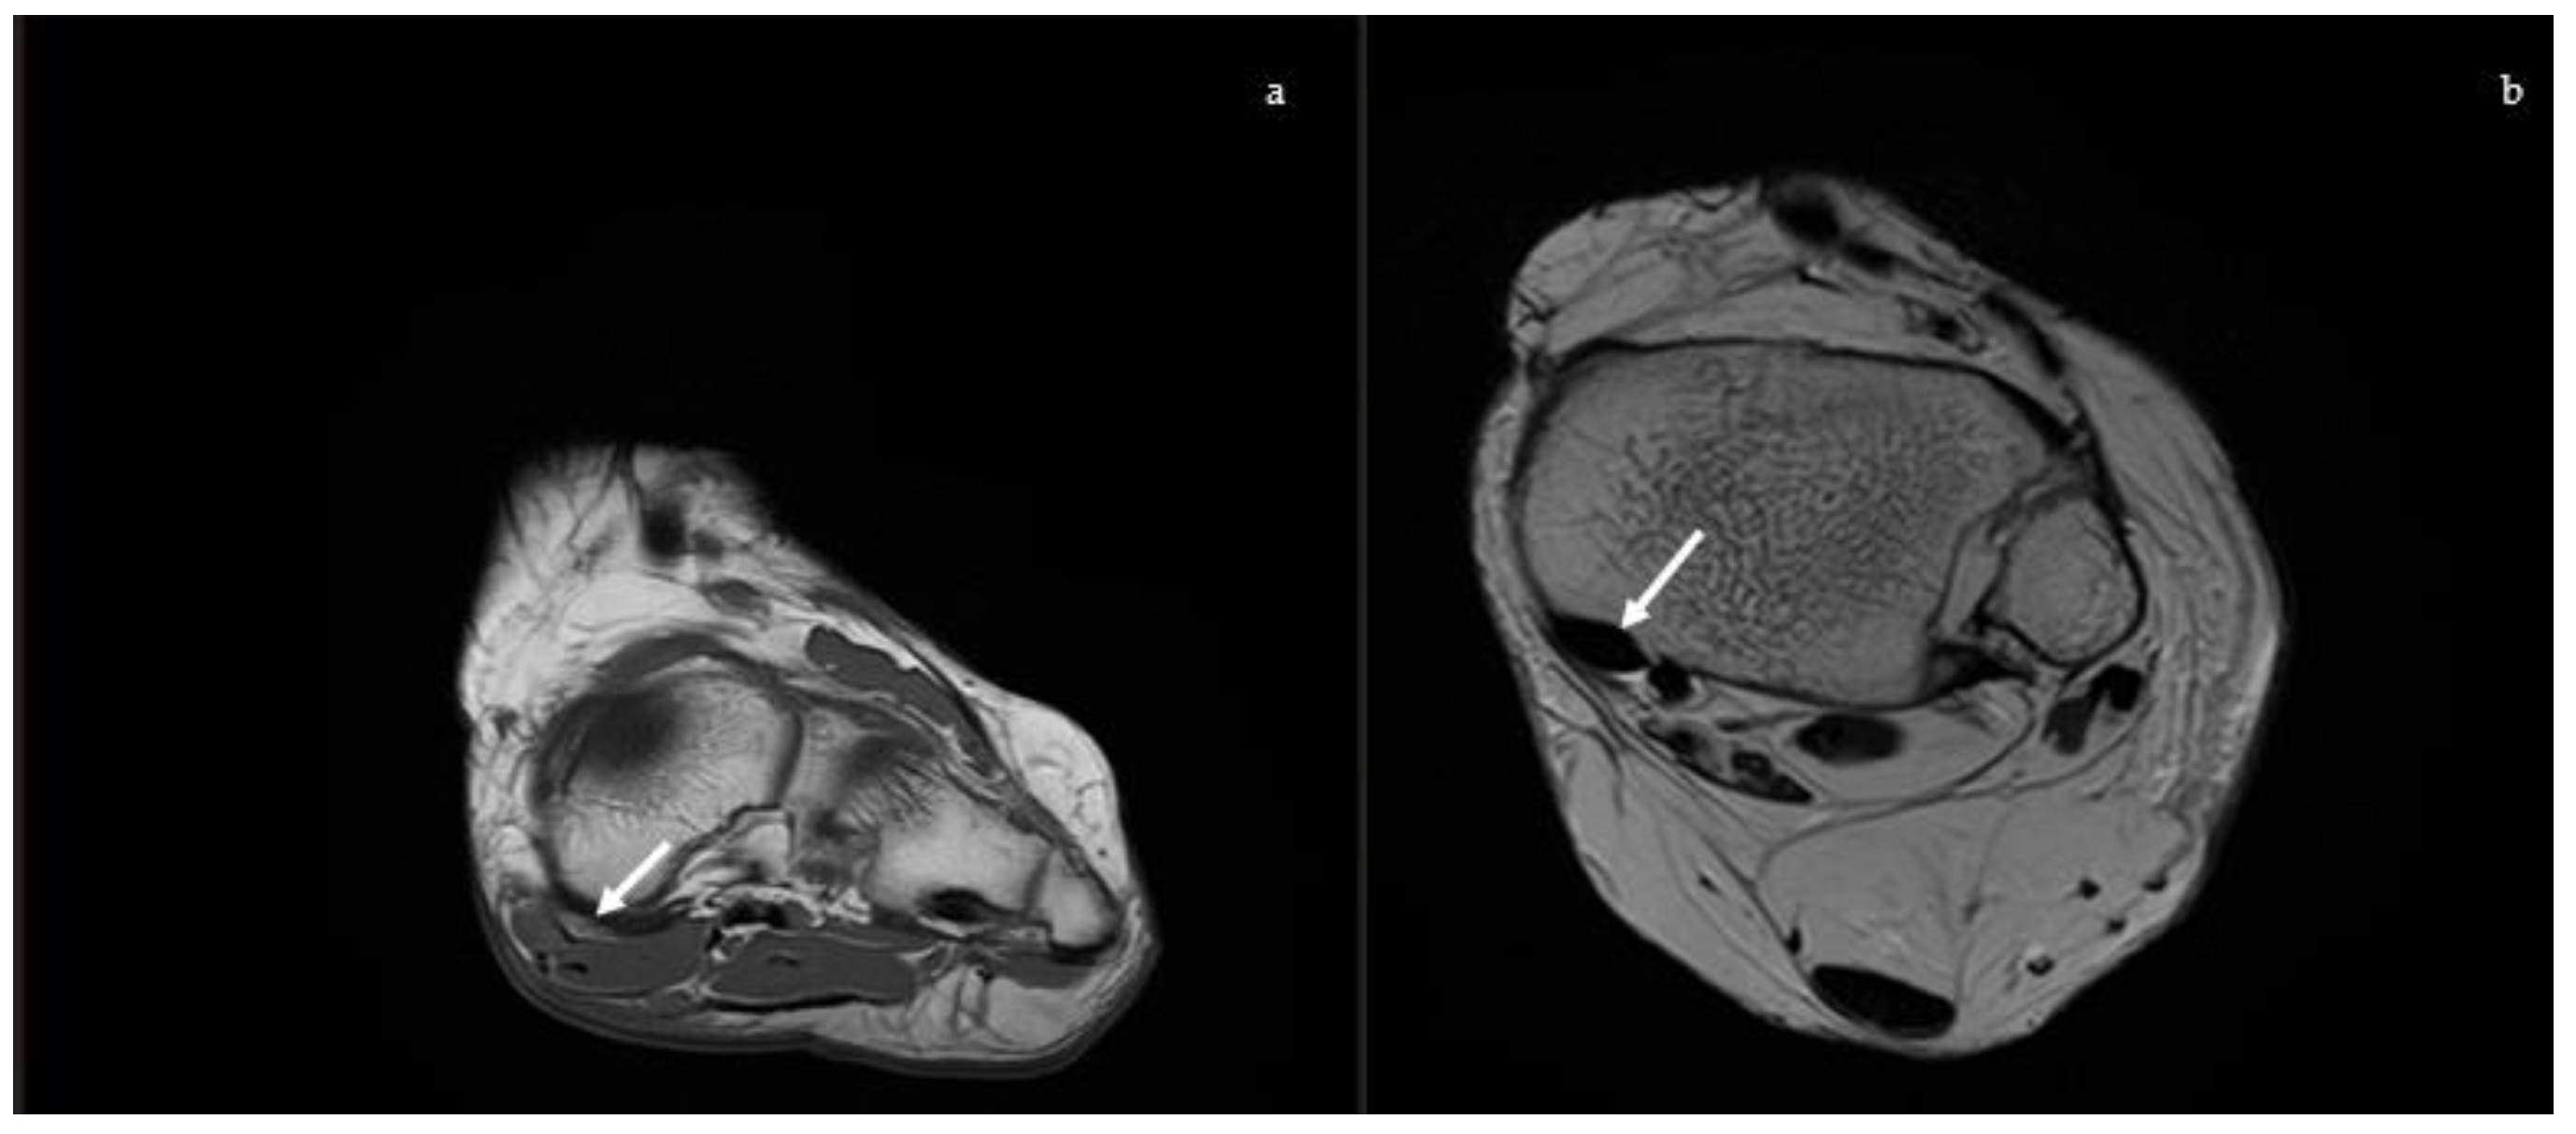

2.2. Magnetic Resonance Imaging (MRI)

2.2.1. Posterior Tibial Tendon

2.2.2. Spring Ligament